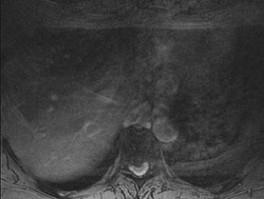

问题 男,65岁,背部疼痛2个月余,MRI检查如图,请选出最可能的诊断 ( )

选项 A、硬膜外纤维化 B、神经根鞘囊肿 C、椎管内肿瘤 D、椎间盘突出 E、椎间盘炎

答案 D